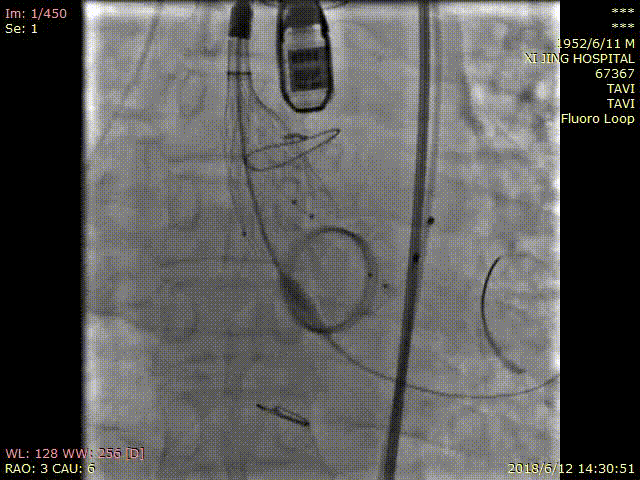

综上,我们制定手术策略:首先局麻状态下经导管逆行封堵二尖瓣瓣周漏,随后在全麻状态下经股动脉标准位植入26mmVenus-A瓣膜。

手术过程

术中DSA影像:

造影检查瓣周漏

TAVR术后造影无瓣周漏

该手术全程顺利,总用时122min,患者术后当天血红蛋白尿消失,无明显瓣周漏,无卡瓣及传导阻滞发生,患者恢复良好,胸闷气短症状消失,并于术后5天出院。